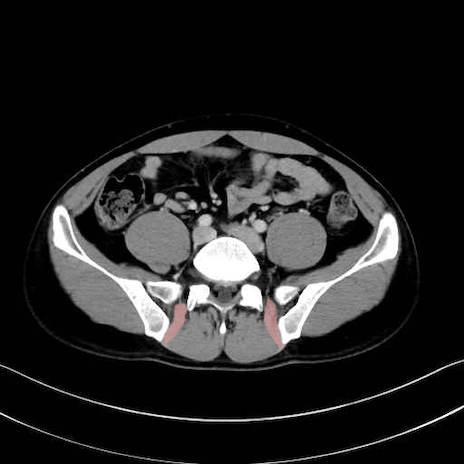

内閉鎖筋 (Obturator internus)